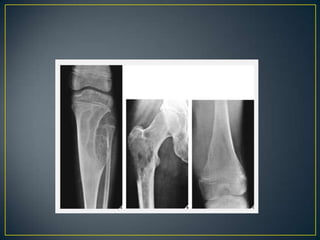

• The site of a bone lesion is an important feature, because

some tumors have a predilection for specific bones or

specific sites in the bone .The sites of some lesions are

so characteristic that a diagnosis can be suggested on

this basis alone, as in the case of parosteal

osteosarcoma or chondroblastoma . Moreover, certain

entities can be readily excluded from the differential

diagnosis on the basis of the lesion's location

• Only two of these—osteoblastic and cartilaginous

tissue—can usually be clearly demonstrated

radiographically.

• Identification of tumor bone within or adjacent to the area

of destruction should alert the radiologist to the possibility

of osteosarcoma/reactive sclerosis.

• Osteosarcoma-cloudy - cotton like fluffy deposits.

• Cartilage is identified by the presence of typically

popcorn-like, punctate, annular, or comma-shaped

calcifications in lobules.

• A completely radiolucent lesion may be either fibrous or

cartilaginous .